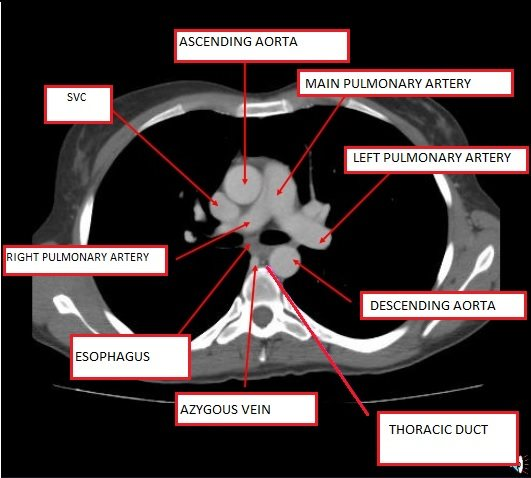

Let's start with the mediastinum, specifically at the level of the sternal angle (T4/T5), which is where all the action happens. I'll find a clear diagram for you to visualize these structures.

That's a perfect view of the "T4 level" structures. Notice how the arch of the aorta and the bifurcation of the trachea are the stars of the show here.